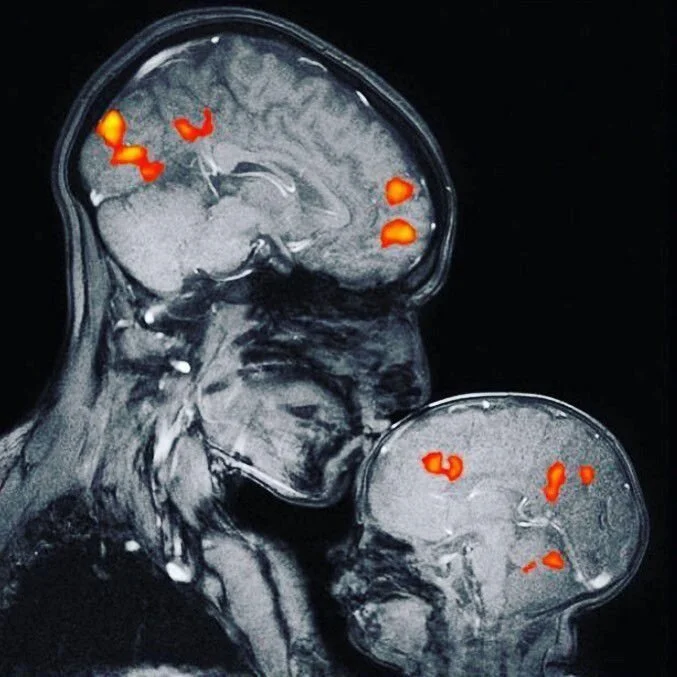

Scanner d'un parent et son enfant montrant leur activité cérébrale

L’ocytocine est produite par l’hypothalamus et libérée par l’hypophyse. Elle joue un rôle essentiel dans les relations sociales, les liens affectifs et le sentiment de confiance.